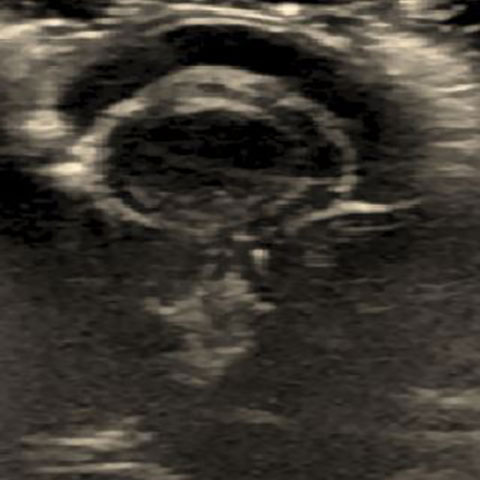

水晶体脱臼と網膜はく離の症例(猫、腎障害)

エコー画像

後方脱臼と、前方脱臼がある。眼球摘出(当院でも可能)が治療法。